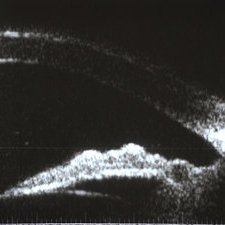

Sarcoidosis Panuveitis Slide 4

Oct 22 2012 by Ronald C. Gentile, MD

High frequency ultrasound biomicroscopy of the anterior chamber and angle images a granuloma involving the iris root and Bussaca nodules on the iris surface consistent with granulomatous uveitis.

Photographer: The New York Eye & Ear Infirmary Department of Medical Imaging

Condition/keywords: sarcoid granuloma, sarcoidosis panuveitis